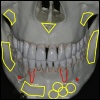

Grundsätzlich eignen sich Implantate in den unterschiedlichsten Fällen, angefangen vom Ersatz eines einzelnen Zahnes bis hin zum Ersatz aller Zähne im völlig zahnlosen Kiefer. Obwohl jeder Patientenfall individuell unterschiedlich ist, so lassen sich doch sehr gut anhand der verschiedene Lückengebisssituationen die Versorgungstypen einteilen.

Viele Zähne fehlen Wenn mehrere Zähne fehlen, so ist es mit Implan...

Freiendsituation Sind mehrere Seitenzähne verlorengegangen, so e...